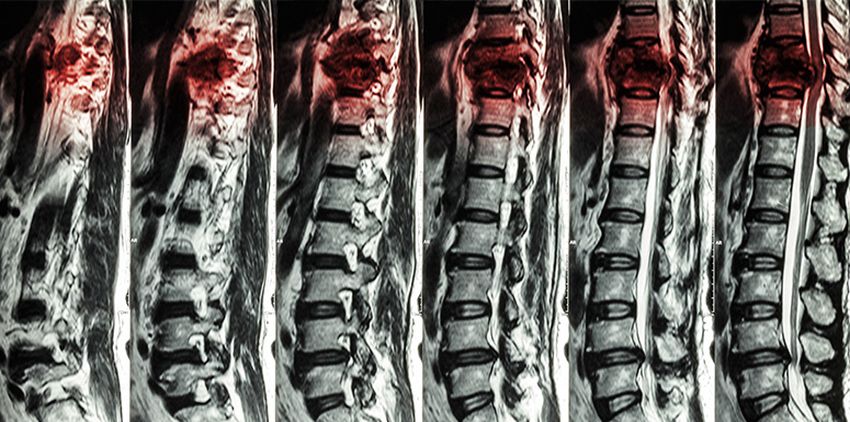

Similar to the brain, the human spinal cord cannot regrow cells. Therefore, some spinal cord symptoms may appear immediately, and others may appear over time. The symptoms of spinal cord vary depending on the severity of it. Based on the degree of the injury and the location where it occurred, the symptoms usually include the following:

All spinal cord injuries are unique. To know exactly what type you suffered, you should see a doctor as soon as possible.